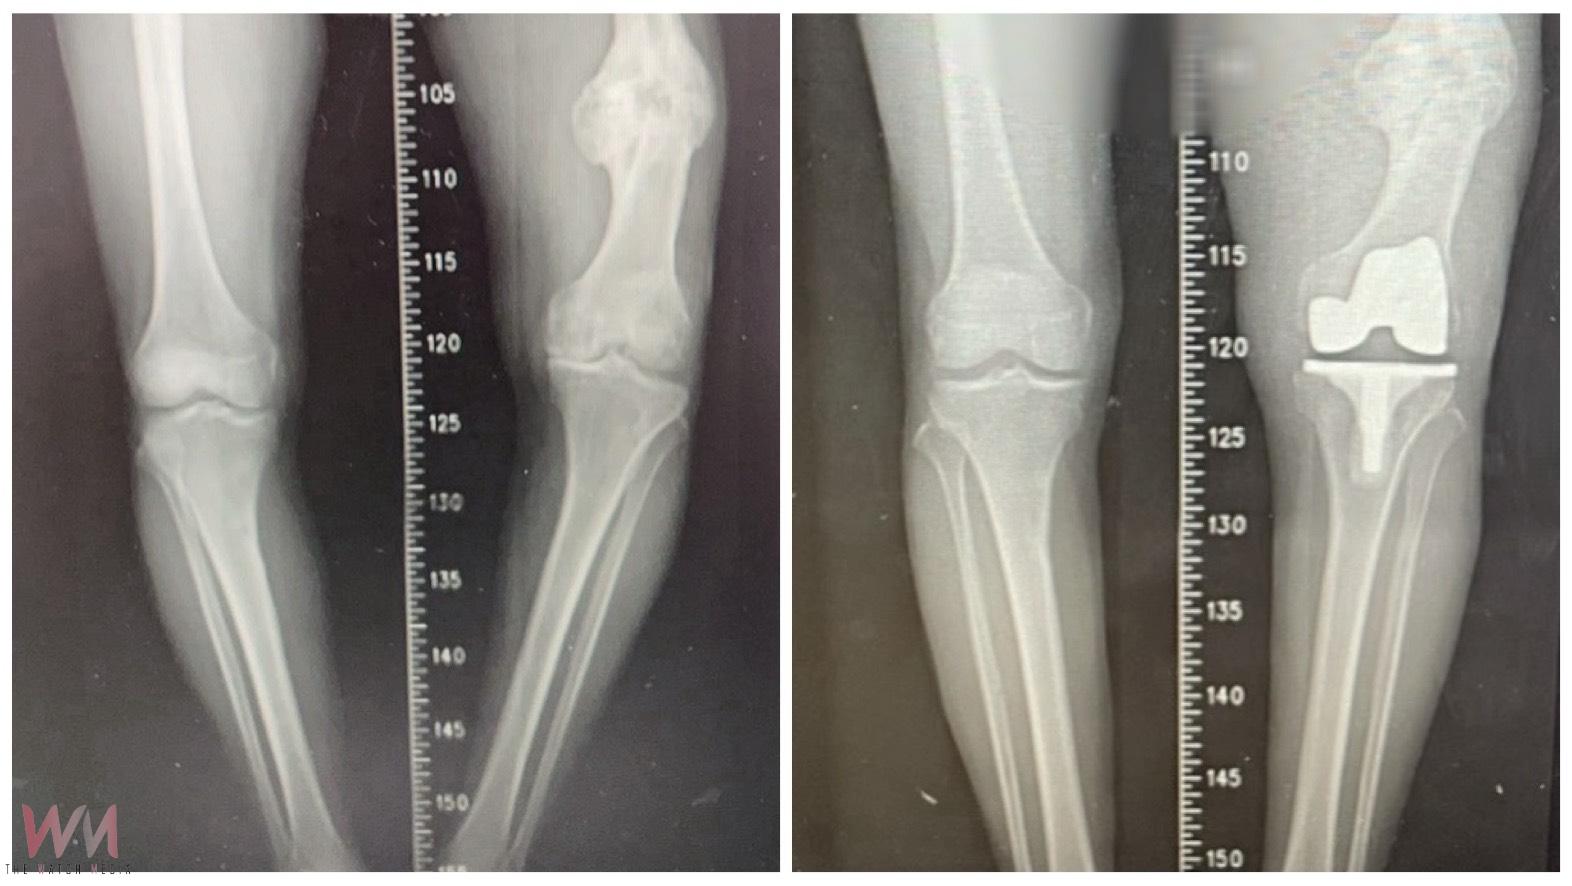

(觀傳媒中彰投新聞)【記者廖妙茜/台中報導】豐原87歲黃先生,長年深受長短腳與膝蓋疼痛所苦,他年輕時左側股骨骨折,當時治療不佳導致骨癒合不良並出現內翻變形,最初兩下肢僅有約 2 公分長度差距,隨著時間推移逐漸惡化,最後擴大至近7公分,讓他不僅步態不穩,更引發腰部與下肢不適,經衛生福利部豐原醫院骨科江福財醫師評估,決定進行人工膝關節置換手術,最終成功改善症狀,讓黃先生重拾穩健步伐。

江福財醫師進一步說明,本次手術的困難在於同時面對「陳舊性股骨骨折造成的骨骼變形」與「長達 7 公分的下肢長度差距」,此次手術除了進行人工關節置換,還需進行精準的韌帶平衡,江醫師解釋,輔以電腦導航與影像輔助技術,得以在修正骨骼角度的同時兼顧關節周圍韌帶平衡,避免造成膝關節不穩定,行動困難,手術並未採用截骨矯正方式,而是單靠人工膝關節置換,直接解決患者最在意的長短腳問題,最終成功將雙腿長度差縮小至約 2.5 公分,大幅改善步態,術後患者無需輔具即可下床行走,逐步恢復生活自理能力。江醫師提醒,術後必須持續進行肌力訓練與步態矯正,以確保關節穩定性,並定期回診追蹤,以獲得最佳治療成效。